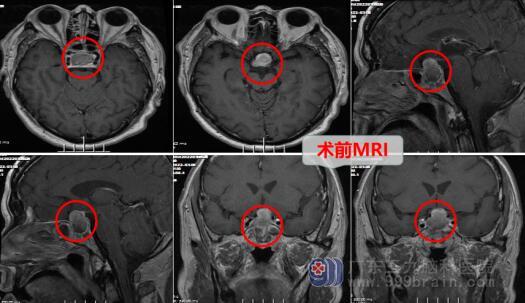

原来,钟先生因为多饮多尿、头晕等症状到广东三九脑科医院进行检查后被诊断为颅内鞍区占位。

听完医生解释,钟先生在完善了相关检查与术前准备后,接受了神经外十科团队为他行“内镜经鼻蝶鞍区占位病变”,手术很顺利,肿瘤被完整的切除了。术后的钟先生精神良好,没有明显的不适,顺利进入了康复阶段。